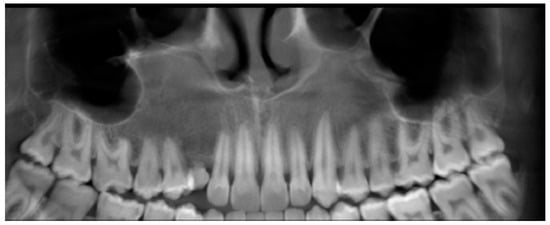

The AOT case refers to 2018 when a 14-year-old male patient was referred to the Department of Oral and Maxillo-Facial Sciences of the Sapienza University of Rome with pain and swelling in the right maxilla. Clinical examinations showed a single 4 × 4 cm swelling on the labial aspect of the right maxillary alveolus in relation to teeth 12 to 17. The overlying mucosa was normal (Figure 1). On palpation, the swelling was bony, hard and non-tender. Radiographic examinations such as panoramic X-ray and computed tomography scan (Figure 2) showed a demarcated unilocular radiolucent lesion extending from 1.2 to 1.7 with a permanent canine embedded within the lesion and pushed away from its normal position. The possibilities of follicular cyst or odontogenic tumor were considered clinically.

Figure 2. Radiographic examinations, such as panoramic X-ray (a) and computed tomography scan (b), reveal a well-defined, single-chambered radiolucent lesion spanning from 1.2 to 1.7, with a permanent canine embedded within the lesion and displaced from its usual position.